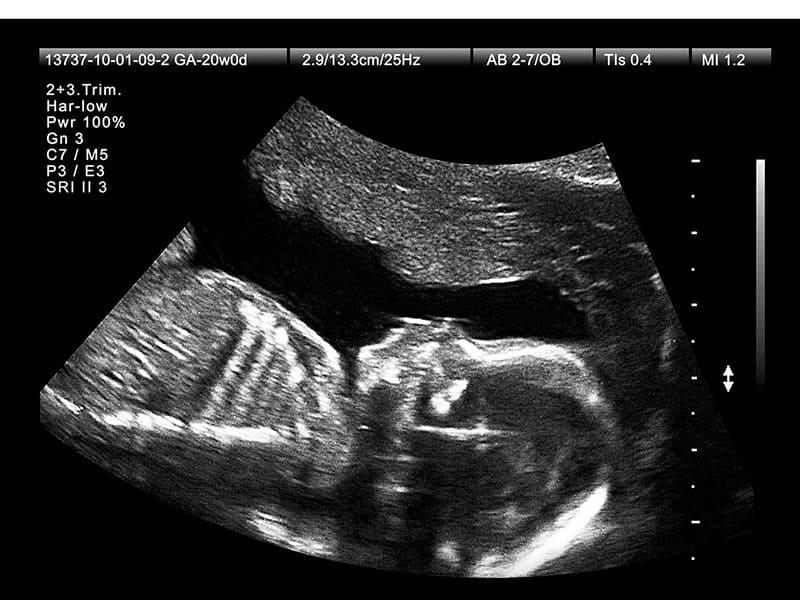

Chỉ số OFD (đường kính chẩm – trán) có thể được đo trong hầu hết các lần siêu âm thai, nhưng sẽ có ý nghĩa rõ rệt hơn ở những giai đoạn nhất định. Ngay từ quý 2 của thai kỳ, hộp sọ và não bộ đã phát triển rõ ràng, vì vậy bác sĩ thường bắt đầu chú ý nhiều hơn đến chỉ số này. OFD thường được sử dụng kết hợp với BPD để đánh giá hình dạng đầu, chu vi vòng đầu và sự phát triển não bộ thai nhi.

- Từ tuần 18–22 (siêu âm hình thái học): giai đoạn quan trọng nhất để đo OFD, kết hợp các chỉ số khác nhằm phát hiện bất thường về não – sọ.